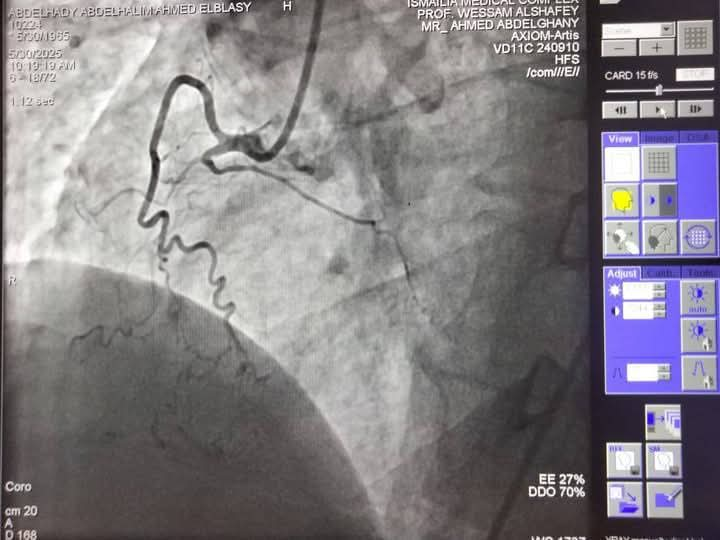

تمكن فريق قسطرة القلب في مجمع الإسماعيلية الطبي من إنهاء معاناة حالتين متوسط عمرهما 60 عامًا، كانتا تعانيان من أعراض متكررة لأزمات قلبية، بعد إجراء قسـطرة تشخيصية.

الحالتان كانتا تعانيان من انسداد في الشريان التاجي

وتبين وجود انسداد كلي مزمن في الشريان التاجي CTO-RCA، مما استدعى التدخل العاجل نظرًا لتعقيد وخطورة الحالات، وتحت إشراف خبير قسطرة الشرايين التاجية المعقدة بمجمع الإسماعيلية الطبي، وهما الأستاذ الدكتور وسام الدين الشافعي، تم إجراء قسطرة علاجية ناجحة لكلا الحالتين، حيث تم استخدام تقنيات حديثة تشمل توسيع الشرايين بالبالونات الدوائية وتركيب دعامتين دوائيتين للحالة الأولى، وثلاث دعامات للحالة الثانية.